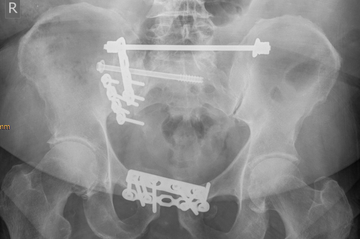

Beckenfrakturen

Beckenfrakturen und Frakturen der Hüftgelenkspfanne (Azetabulum) sind komplizierte, teilweise sogar lebensbedrohende Verletzungen. Schwere, instabile Beckenbrüche treten häufig in Verbindung mit Hochenergieverletzungen wie einem Polytrauma auf. Gefäß- und Nervenverletzungen sind in deren Folge nicht selten und können zu einem massiven Blutverlust führen. Die Erstversorgung hängt von der Schwere der Fraktur und der Begleitverletzungen ab. Bei schweren Verletzungen ist zunächst eine Stabilisierung mit einer Beckenzwinge oder einem Fixateur externe notwendig, um andere Verletzungsfolgen primär zu behandeln.

Zur weiterführenden Diagnostik einer Beckenverletzung steht uns modernste radiologische Bildgebung mit 3D-Rekonstruktion zur Verfügung. Auch intraoperativ ist eine 3D-Bildgebung bei laufender Operation möglich. Zur Therapie von vorderen und hinteren Beckenring-Frakturen favorisieren wir Platten-Osteosynthesen offener Reposition, aber auch minimal-invasive Therapieoptionen und transkutane Verschraubungen.

Frakturen der Hüftgelenkspfanne

Frakturen der Hüftgelenkspfanne (Azetabulumfrakturen) sind häufig komplizierte Frakturen. Die Schwierigkeit der Versorgung liegt in der exakten Wiederherstellung der konkaven Gelenkfläche. Auch bei optimaler Versorgung kann sich aus einer Azetabulumfraktur ein frühzeitiger Hüftgelenksverschleiß entwickeln.

Die Therapie-Entscheidung berücksichtigt die individuelle Situation des Verletzten wie Lebensalter, Knochenqualität, körperliche Aktivität u.v.m. und bedarf hoher operativer Erfahrungen. Neben den oben genannten Verfahren kommt auch die sofortige endoprothetische Versorgung mit speziellen Stützschalen in Betracht. Sie gewährleistet gerade bei älteren Menschen eine frühzeitige Mobilisation.